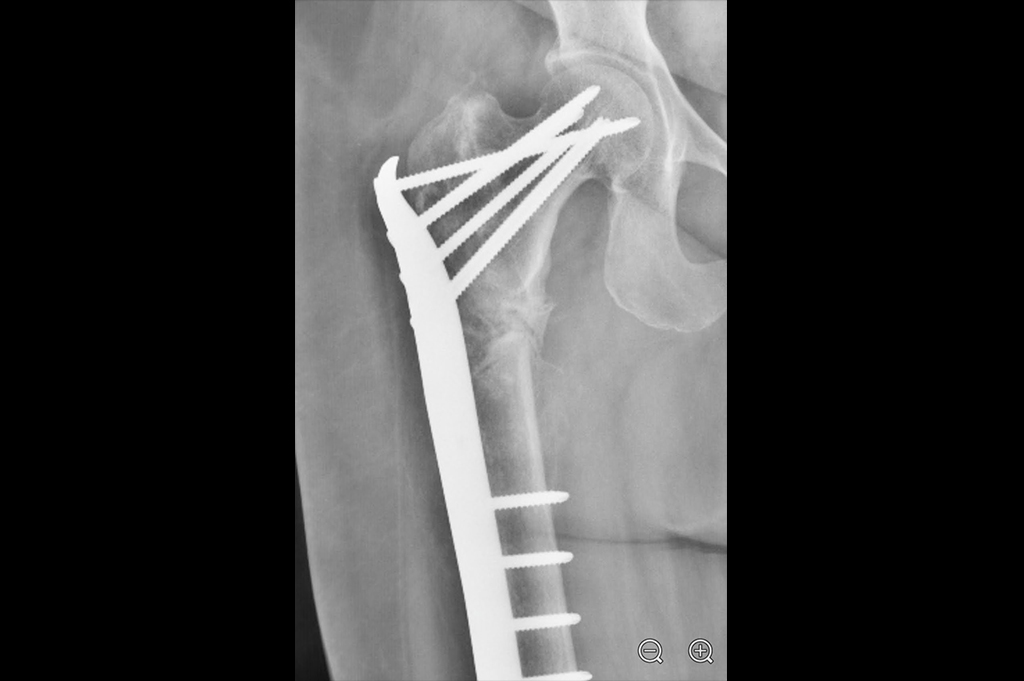

Subtrochanteric Fracture